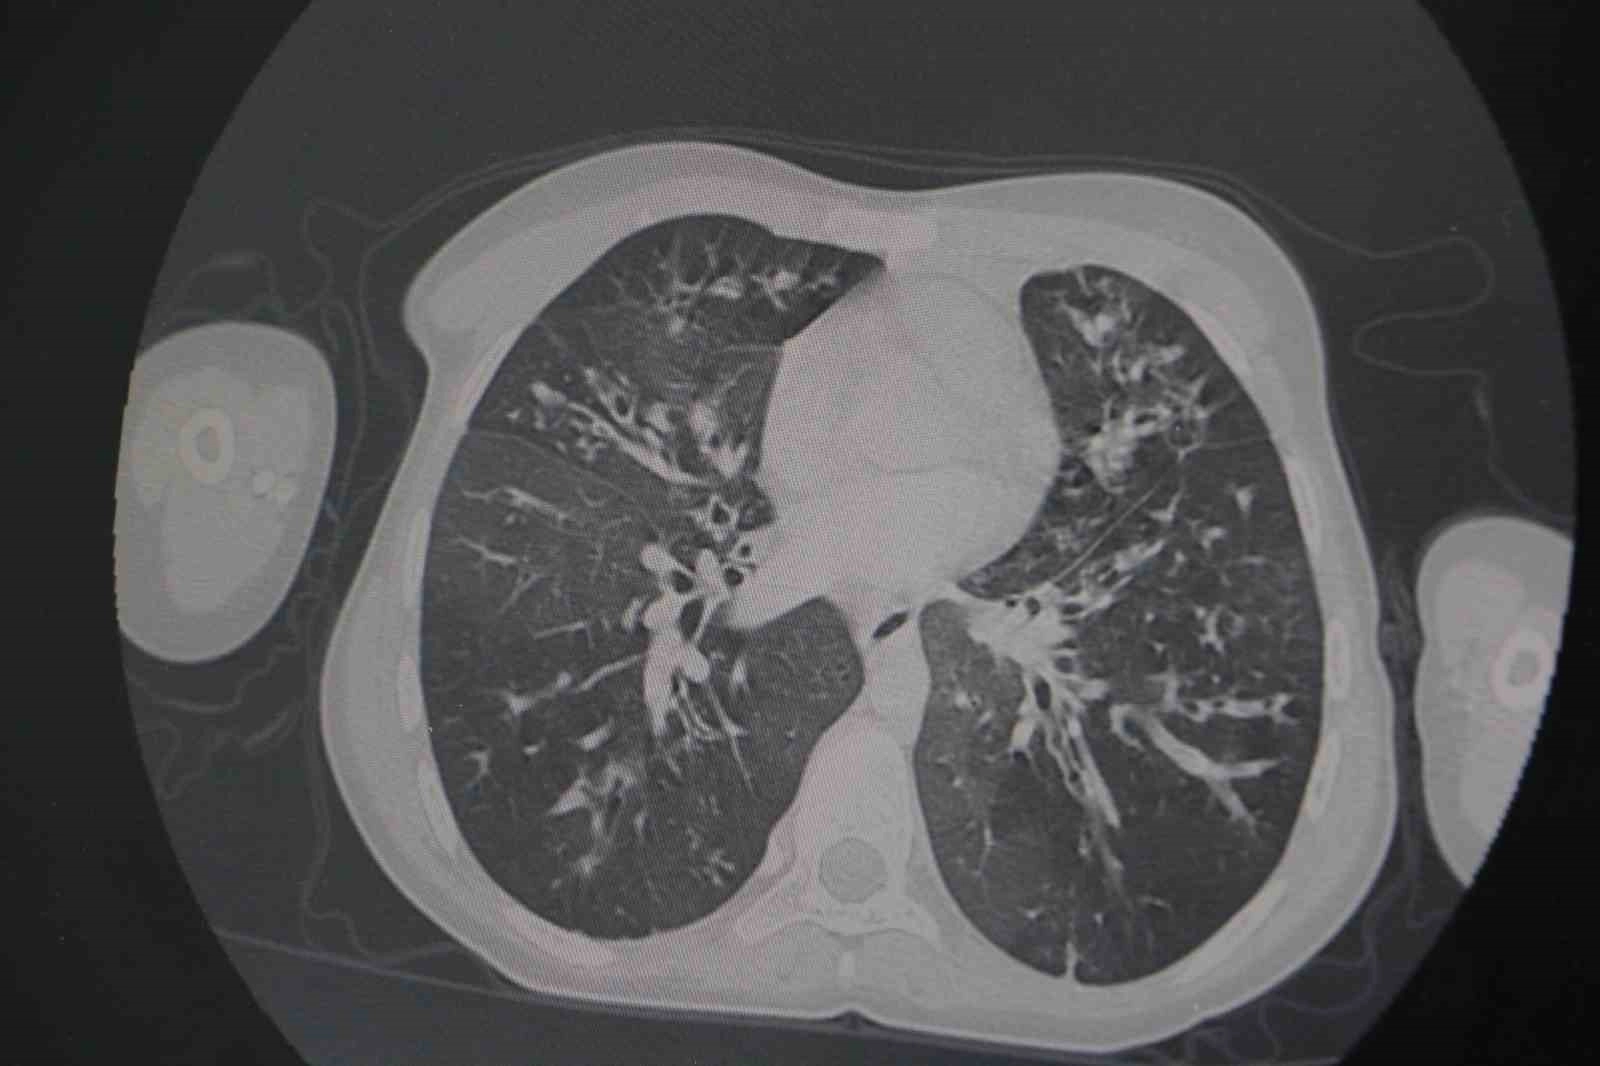

Kistik fibrozis hastalığının en sık akciğer tutulumu yapmakla birlikte mide-bağırsak sistemi ve pek çok sistemleri de tutabilen bir hastalık olduğunun altını çizen Meral, "Biz hastalara ne kadar erken tanı koyarsak bu hastalığın hem ilerlemesinin önüne geçmiş oluyoruz. Takibimizde olan hastaların da uygun şekilde tetkiklerini yaparak koruyucu önlemler alıp en ufak bir enfeksiyon durumunda erken müdahale ederek akciğer hasarının da önüne geçmiş oluyoruz" ifadelerine yer verdi.

Hastaların belirli aralıklarla mutlaka takiplerinin yapılması, uygun şekilde örneklemelerin alınmasının çok önemli olduğunu dile getiren Meral, "Bu aşamada belirli aralıklarla görüntüleme yapıyoruz. Hastaların örneklemelerini alıyoruz. Burada bizim için önemli olan hastaların balgam tahlillerini yapabilmek. Bu tahliller neticesinde enfeksiyonlar olabilir. Bu hasta grubunun en önemli sorunu zaten dirençli enfeksiyonlar olmasıdır. Bu dirençli enfeksiyonlar için erken dönemde tedaviye başladığımız zaman daha da direnç kazanmasının önüne geçmiş oluyoruz. Bu nedenle bu hastaların belirli aralıklarla mutlaka takiplerinin yapılması, uygun şekilde örneklemelerin alınması önemlidir. Biz de zaten hastanemizde bu hastalarımızın takibi için ayrı bir oda ve birim oluşturduk" diye konuştu.